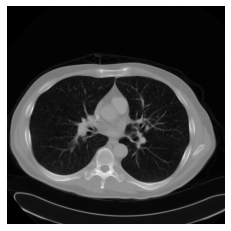

W efekcie otrzymujemy i obraz: